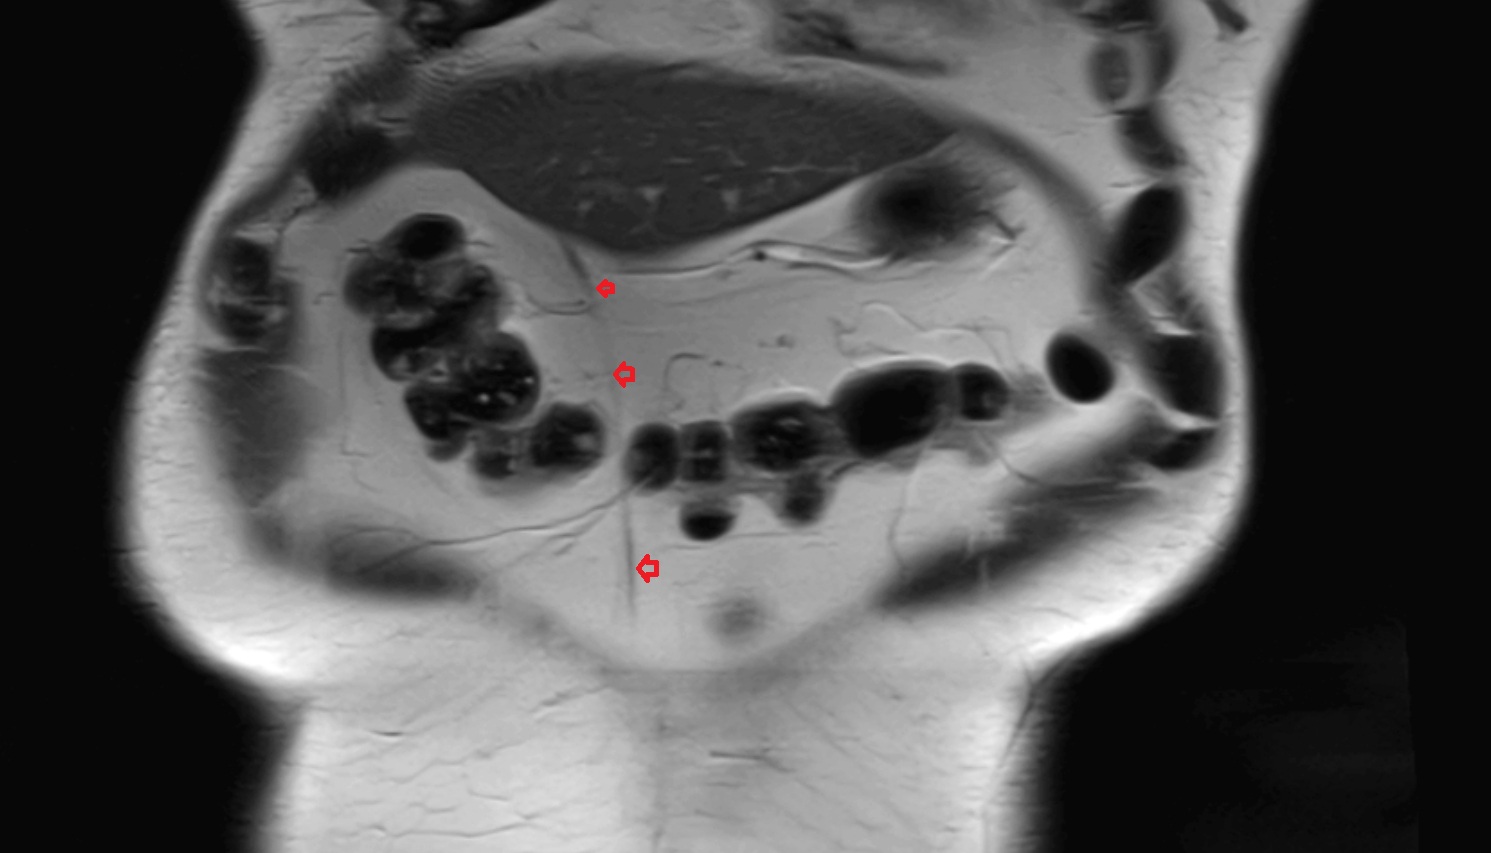

- Ovaries

- Right ovary

- Left ovary